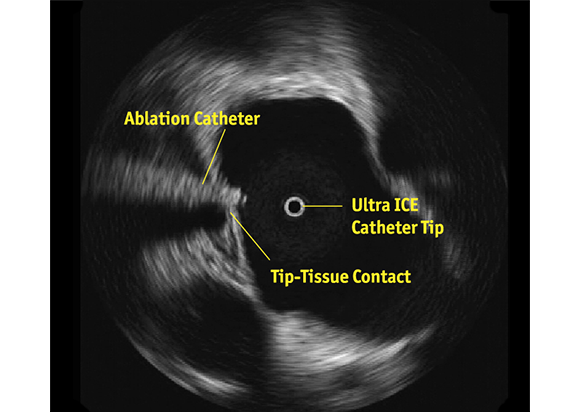

Crossing to the Septum to Help Guiding Left Sided Procedures

A key application for the ULTRA ICE PLUS catheter involves crossing the septum and then monitoring and helping to guide left-sided procedures. In this setting, ULTRA ICE PLUS catheter is designed to allow the user to:

• Visualize left atrial anatomy

• Confirm catheter location relative to the anatomy

• Verify tip-to-tissue contact

• Identify location of the esophagus relative to the ablation catheter

• Characterize acute lesion morphology: swelling, dimpling, and crater formation

• Monitor for any early signs of thrombus formation, stenosis, or pericardial effusion